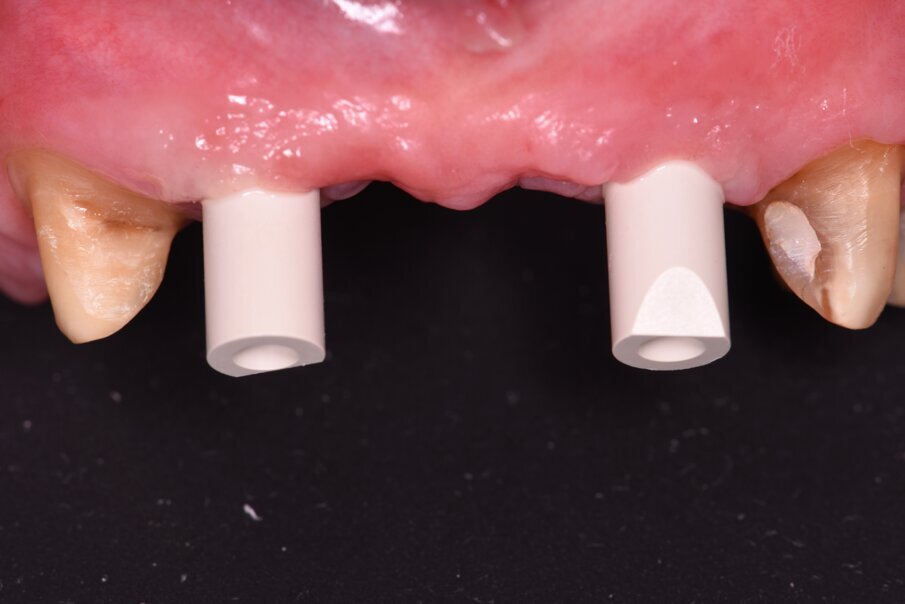

La rigenerazione ossea è stata ottenuta secondo l’impiego di biomateriale di origine bovina demineralizzato e stabilizzato con una membrana a lento riassorbimento in pericardio nativo fissata con dei chiodini in titanio (Fig. 23). Com’è noto la stabilità dell’innesto è un requisito indispensabile per ottenere una reale rigenerazione ossea stabile nel tempo. Dopo 4-6 mesi si effettua una radiografia di controllo eseguendo successivamente un opercolo perimplantare. In questo caso data la lieve deiscenza presente si è optato per l’impiego di un diatermocoagulatore per limitare il danno biologico ai tessuti limitrofi e mantenere inalterata la rivascolarizzazione della sede, inoltre non essendo un materiale metallico ma bensì ceramico, l’eventuale contatto viene disperso e non assorbito dall’impianto (Fig. 24). Data l’ottima stabilizzazione funzionale e volendo contenere i costi viene realizzata un’impronta digitale dell’arcata col primo provvisorio in situ e alla sua rimozione un’impronta dell’intera arcata con e senza gli scan body implantari (Fig. 25). Per mantenere l’opercolo ottenuto si utilizzano delle cappette di guarigione sempre in Zirconia che serviranno anche per stabilizzare i tessuti perimplantari (Fig. 26).

Fig. 25_Dopo opercolarizzazione si provvede a rilevare l’impronta con appositi transfer che per le impronte digitali si chiamano scan body e si differenziano per il tipo di impianto e per il tipo di scanner intraorale utilizzato.

Fig. 26_Al termine dell’impronta si posizionano delle cappette di guarigione in zirconia in grado di stabilizzare il tessuto gengivale.